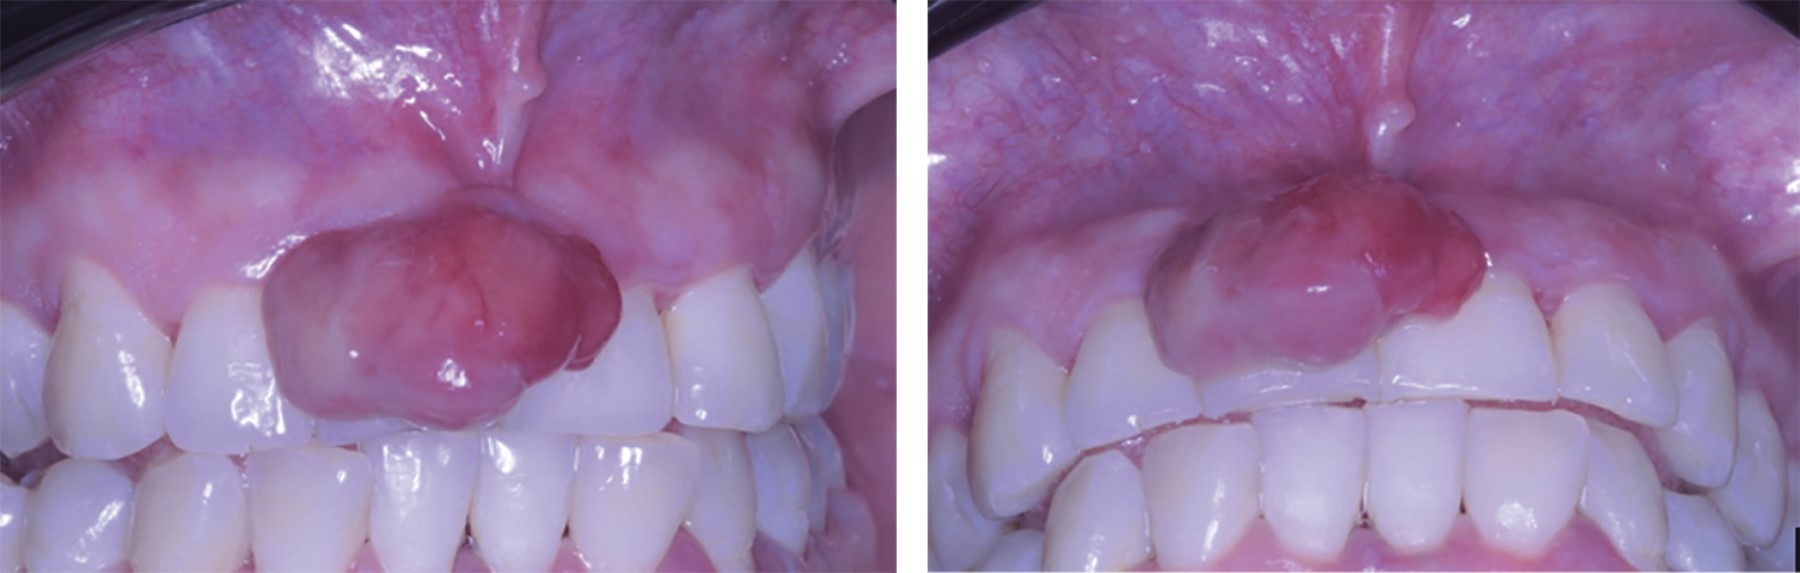

Se trata de paciente femenino de 31 años, quien acude a la Clínica de Enseñanza Comunitaria de la Universidad Autónoma de Sinaloa por presentar en los dientes centrales un aumento de volumen en la zona vestibular de la arcada superior. A la anamnesis, la paciente no presenta antecedentes heredofamiliares de relevancia para su padecimiento actual. El examen intraoral reveló una masa gingival de forma ovalada, pediculada, eritematosa, no dolorosa, firme a la palpación y aproximadamente de 18 × 13 mm presente en la encía interdental en relación con los centrales superiores. Lesión asintomática y sin mostrar evidencia clínica de ulceración (Figura 1).

Figura 1